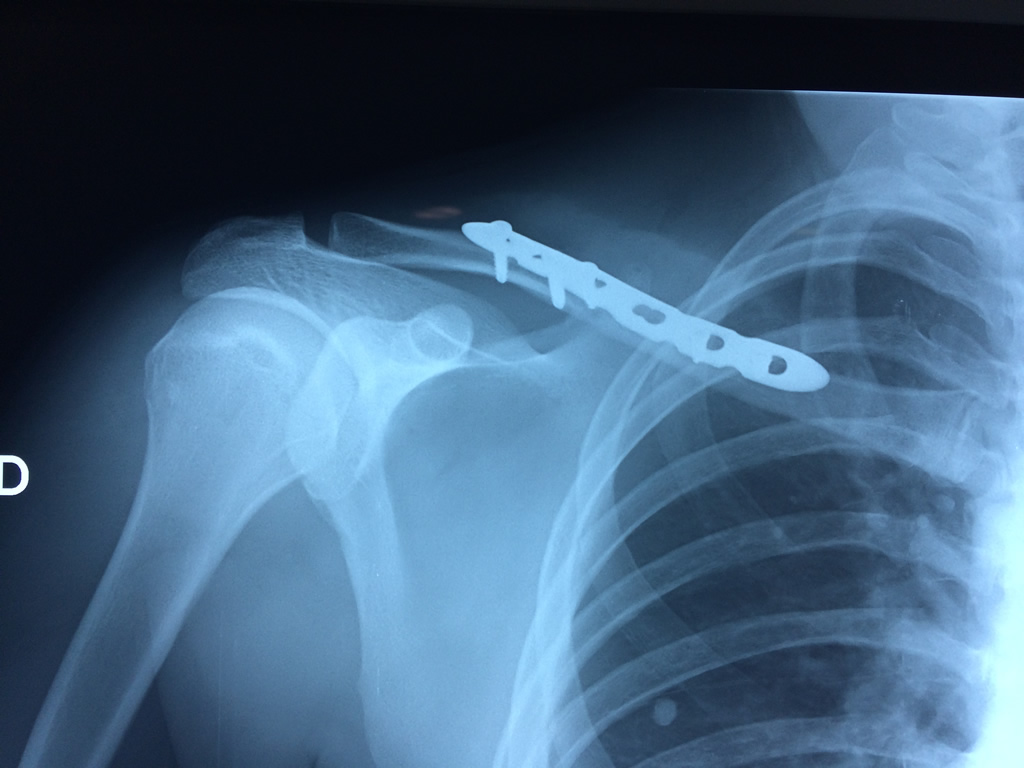

Clavicula 3

Detail Download